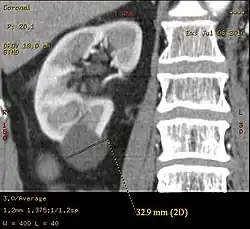

-

Renal ultrasonography of a simple renal cyst with posterior enhancement. -

Advanced polycystic kidney disease with multiple cysts.[13] -

Renal cyst as seen on abdominal ultrasound -

A very small (8 mm) simple renal cyst. -

Bosniak II cyst at the lower pole of right kidney with septations within.